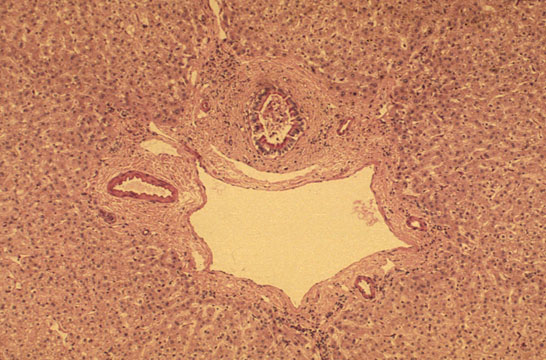

Fig 24 - Portal Space

PORTAL ARTERIOLE: Located close to the portal bile duct.Small arterioles may penetrate into the lobule.

PORTAL VEIN: Large,thin -walled perforates the limiting plate and connects with sinusoids.Terminates at the equator of the acinus were it forms the terminal portal vessel,not visible in normal conditions.

PORTAL BILE DUCT: Identifiable for its location close to the portal arteriole.

CHOLANGIOLES: Called also bile ductules and ducts of Hering are situated at the periphery of the portal space.

PORTAL LYMPHATICS: Invisible,are around vessels and bile ducts.They drain lymph from the Disse spaces to the hilus of the liver connecting with lymphtics from the glissonian capsule.

INFLAMMATORY CELLS: Presence of lymphocytes and macrophages is normal.Presence of polymorphs, eosinophils and plasma cells is abnormal.

CONNECTIVE TISSUE: Consists of interlacing type I collagen fibers.There is elastic tissue which increases with age.

PERIPORTAL LIMTING PLATE:It is a row of small hepatocytes immediately around the portal connective tissue.

SPACE OF MALL: Space between limiting plate and portal field.It contains villi .